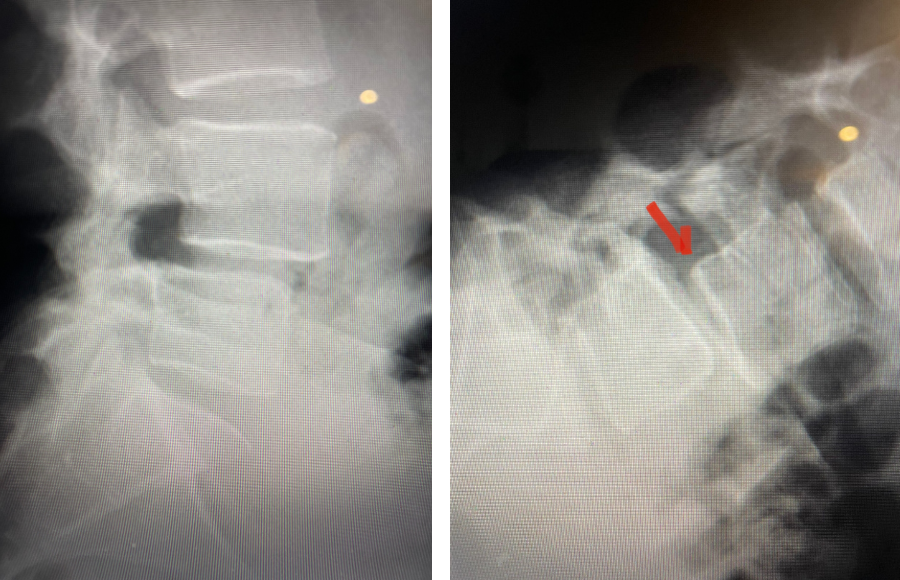

Fig 2: Sagittal T2-weighted MRI of the lumbar spine demonstrating a dysmorphic, trapezoidal-shaped L5 vertebral body (red dot) and a subtle grade 1 spondylolisthesis L5-S1 (blue line).

Fig 3: Sagittal CT scan with bone windows demonstrating an L5 pars defect (blue dot) and abnormal L5-S1 facet complex as well as a normal right pars structure of L5 (red dot).

Another interesting 54-year-old patient presented with low back pain and severe left lower extremity pain over two months. He had a history of falls. The pain in the leg was more bothersome to the patient. The patient had a work-up with an MRI and CT of the lumbar spine. MRI demonstrated a subtle grade 1 spondylolisthesis L5-S1 with a dysmorphic L5 vertebral body (Fig 2). There was a suggestion of a left L5 spondylolysis or defect in the bridge of bone that connects the superior facet process of the segment and the inferior facet process. A CT of the lumbar confirmed this unilateral abnormality which certainly could account for the patient’s left leg pain (Fig 3). This is an unusual finding in that most patients have bilateral pars defects. Patients with L5-S1 often have congenital abnormalities of the lumbosacral junction including weird shaped, elongated or dysplastic facet joints. A subtle L5-S1 spondylolisthesis with an associated smaller and misshapen L5 vertebral body is often associated with L5 spondylolysis. In addition, with a dysmorphic L5 vertebral body, there is secondary disc degeneration at L5-S1 and sometimes at the L4-5 disc with an associated retrolisthesis at L4-5. There is less surface to surface contact of the L4-5 and L5-S1 leading to chronic segmental instability.